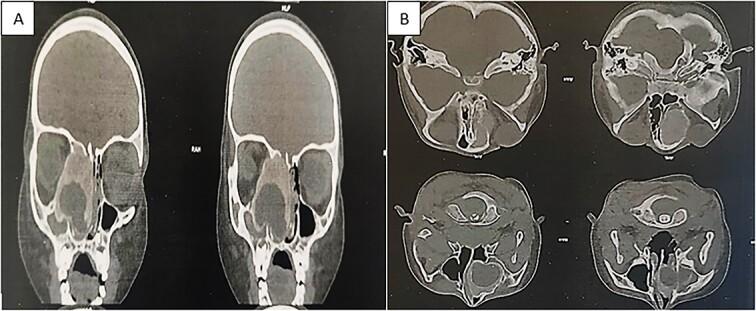

Juvenile ossifying fibroma (JOF) and its variants, including juvenile psammomatoid ossifying fibroma (JPOF), represent rare yet clinically significant benign fibro-osseous lesions that primarily occur in children and young adolescents. They can be found in diverse anatomical sites such as the jaw, nasal cavity, paranasal sinuses, and orbit. JOF exhibits an aggressive nature, necessitating early radiological detection and surgical intervention. Similarly, JPOF, with a locally malignant potential, requires surgical removal, typically conducted through endoscopic approaches. We report a case of a 5-year-old girl with JPOF arising in the ethmoid, revealed by recurrent epistaxis and proptosis. The text emphasizes the importance of early diagnosis through histopathology as a diagnostic tool and underscores the need for appropriate management.

青少年骨化性纤维瘤(JOF)及其变体,包括青少年砂粒样骨化性纤维瘤(JPOF),是罕见但具有临床意义的良性纤维-骨病变,主要发生于儿童和青少年。它们可出现在多种解剖部位,如下颌骨、鼻腔、鼻窦和眼眶。JOF具有侵袭性,需要早期进行影像学检查并采取手术干预。同样,具有局部恶性潜能的JPOF需要手术切除,通常通过内镜手术进行。我们报告了一例5岁女孩,患有起源于筛骨的JPOF,表现为反复鼻出血和眼球突出。本文强调了通过组织病理学作为诊断工具进行早期诊断的重要性,并强调了适当治疗的必要性。